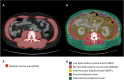

Muscle wasting and low muscle mass are prominent features of protein energy wasting (PEW), sarcopenia and sarcopenic obesity in patients with chronic kidney disease (CKD). In addition, muscle wasting is associated with low muscle strength, impaired muscle function and adverse clinical outcomes such as low quality of life, hospitalizations and increased mortality. While assessment of muscle mass is well justified, the assessment of skeletal muscle should go beyond quantity. Imaging techniques provide the means for non-invasive, comprehensive, in-depth assessment of the quality of the muscle such as the infiltration of ectopic fat. These techniques include computed tomography (CT), magnetic resonance imaging (MRI) and ultrasound. Dual energy X-ray absorptiometry is also an imaging technique, but one that only provides quantitative and not qualitative data on muscle. The main advantage of imaging techniques compared with other methods such as bioelectrical impedance analysis and anthropometry is that they offer higher precision and accuracy. On the other hand, the higher cost for acquiring and maintaining the imaging equipment, especially CT and MRI, makes these less-used options and available mostly for research purposes. In the field of CKD and end-stage kidney disease (ESKD), imaging techniques are gaining attention for evaluating muscle quantity and more recently muscle fat infiltration. This review describes the potential of these techniques in CKD and ESKD settings for muscle assessment beyond that of muscle quantity.